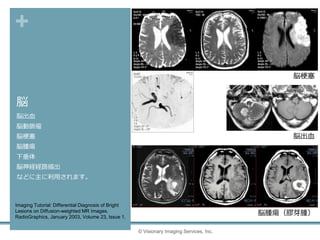

脳

脳出血

脳動脈瘤

脳梗塞

脳腫瘍

下垂体

脳神経経路描出

などに主に利用されます。

© Visionary Imaging Services, Inc.

Imaging Tutorial: Differential Diagnosis of Bright

Lesions on Diffusion-weighted MR Images.

RadioGraphics, January 2003, Volume 23, Issue 1.

脳腫瘍(膠芽腫)